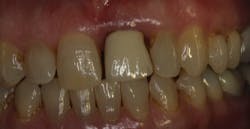

Fig. 2 Buccal view of No. 9

When the patient first presented to the office, she showed normal periodontal measurements around all teeth with the exception of tooth No. 9. (Fig. 1) This tooth had an existing porcelain-to-metal crown that was in traumatic occlusion and with subgingival margins. (Fig. 2) The patient was scheduled to come in for treatment of No. 9; however, prior to that appointment she presented on an emergency basis due to a periodontal abscess associated with that same tooth. (Fig. 3). The tooth had 5 mm to 8 mm pocketing and mobility. Let’s consider the treatment options at this point: